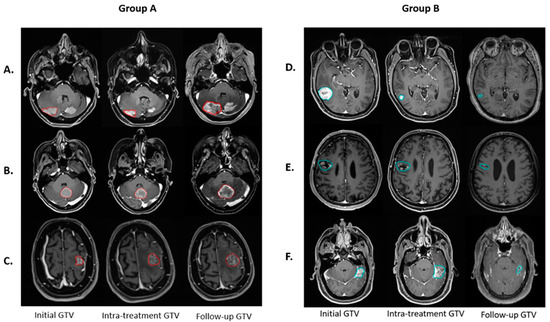

3.1. Treatment Response

| Group A | Group B | p-Value | ||||||

| F1 | Delta Radiomics | Original | shape | Least Axis Length | −1.34382 | −0.231 ± 0.233 | 0.059 ± 0.468 | <0.05 * |

| F2 | 1st Dosiomics | Wavelet-LHL | glszm | Low Gray Level Zone Emphasis | −1.23960 | −0.58 ± 0.867 | 0.148 ± 0.994 | <0.05 * |

| F3 | 2nd Radiomics | Wavelet-LHH | glcm | Correlation | −1.17479 | −0.577 ± 0.584 | 0.147 ± 1.043 | <0.05 * |

| F4 | 2nd Radiomics | Original | glrlm | Long Run Low Gray Level Emphasis | −0.78866 | −0.444 ± 0.195 | 0.113 ± 1.098 | <0.05 * |

| F5 | Delta Radiomics | Wavelet-HHH | gldm | Large Dependence High Gray Level Emphasis | −0.32663 | −0.597 ± 0.951 | 0.152 ± 0.765 | <0.05 * |

| F6 | Delta Radiomics | Wavelet-HHH | glszm | Gray Level NonUniformity | −0.43211 | −0.379 ± 0.674 | 0.096 ± 0.497 | <0.05 * |

| F7 | 1st Radiomics | original | glcm | MCC | 0.51466 | 0.146 ± 0.812 | −0.037 ± 1.054 | 0.486 |

| F8 | Delta Radiomics | Wavelet-LLH | firstorder | Median | 0.69508 | 0.558 ± 1.214 | −0.142 ± 1.086 | 0.064 |

| F9 | Delta Radiomics | Wavelet-HLL | firstorder | Kurtosis | 1.09794 | 0.254 ± 0.831 | −0.065 ± 0.326 | 0.181 |